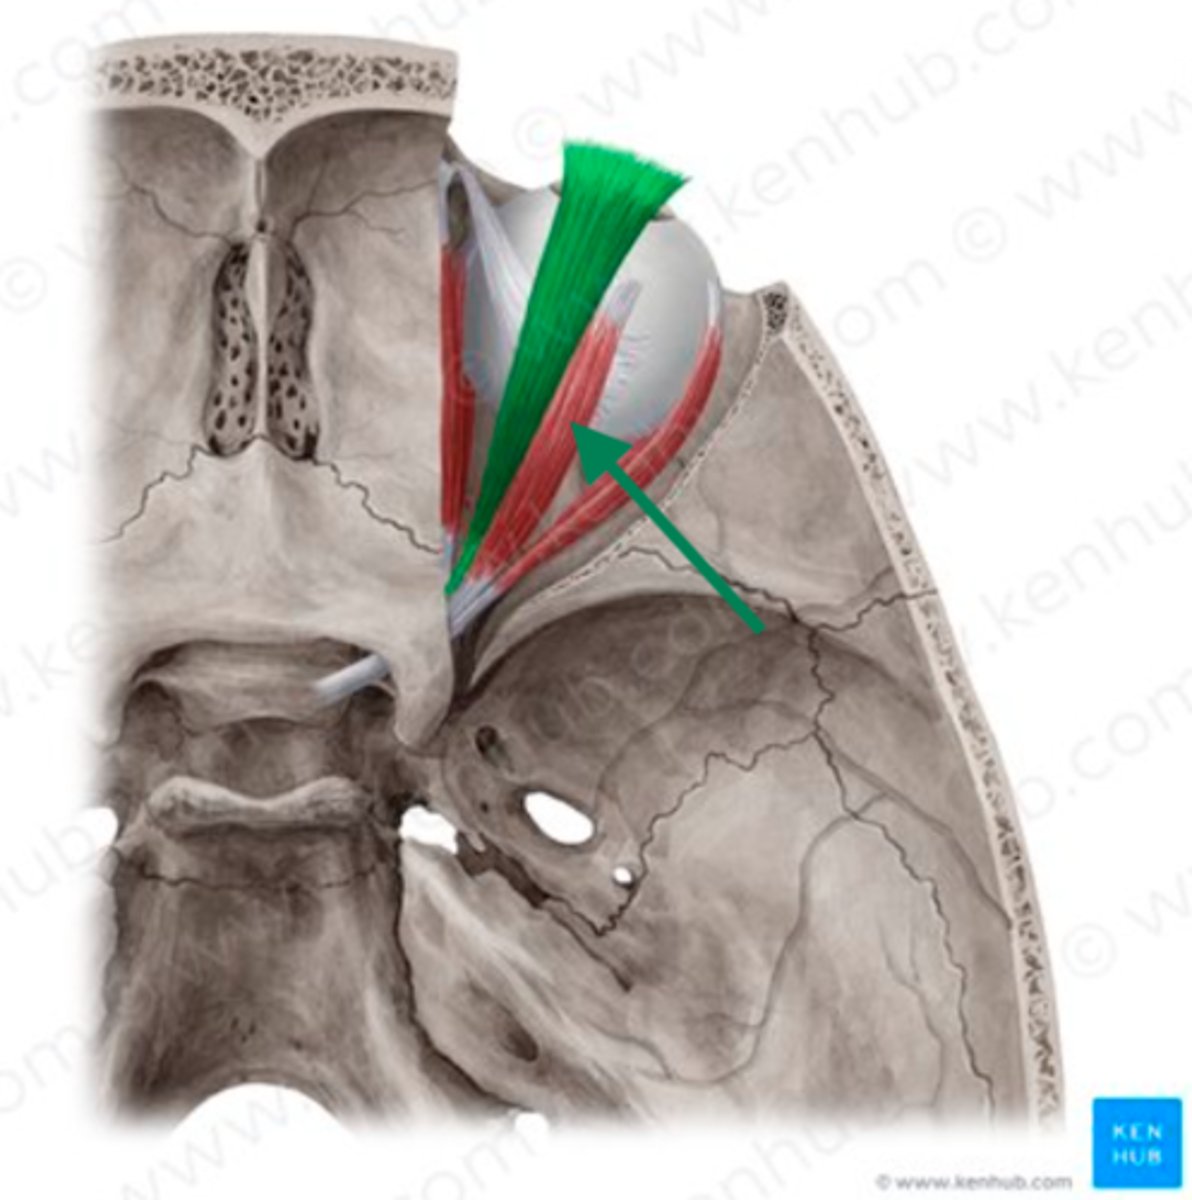

levator palpebrae superioris

superior rectus

superior oblique

superior rectus

cribriform plate